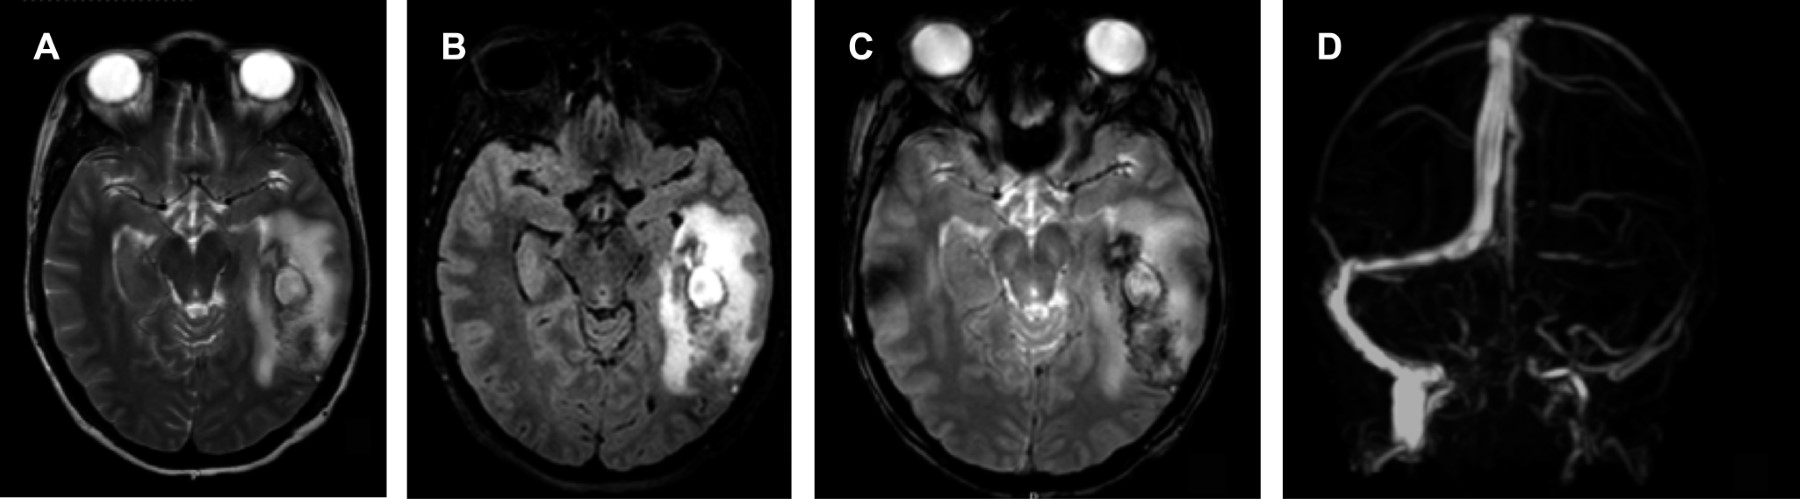

Cerebral venous thrombosis

Figure 1